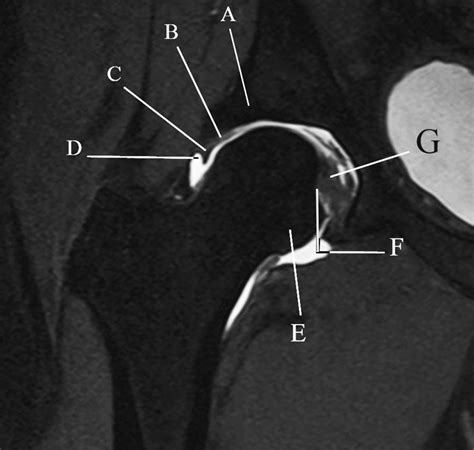

• mri knee joint anatomy

• axial mri knee anatomy

• radiological anatomy of knee joint